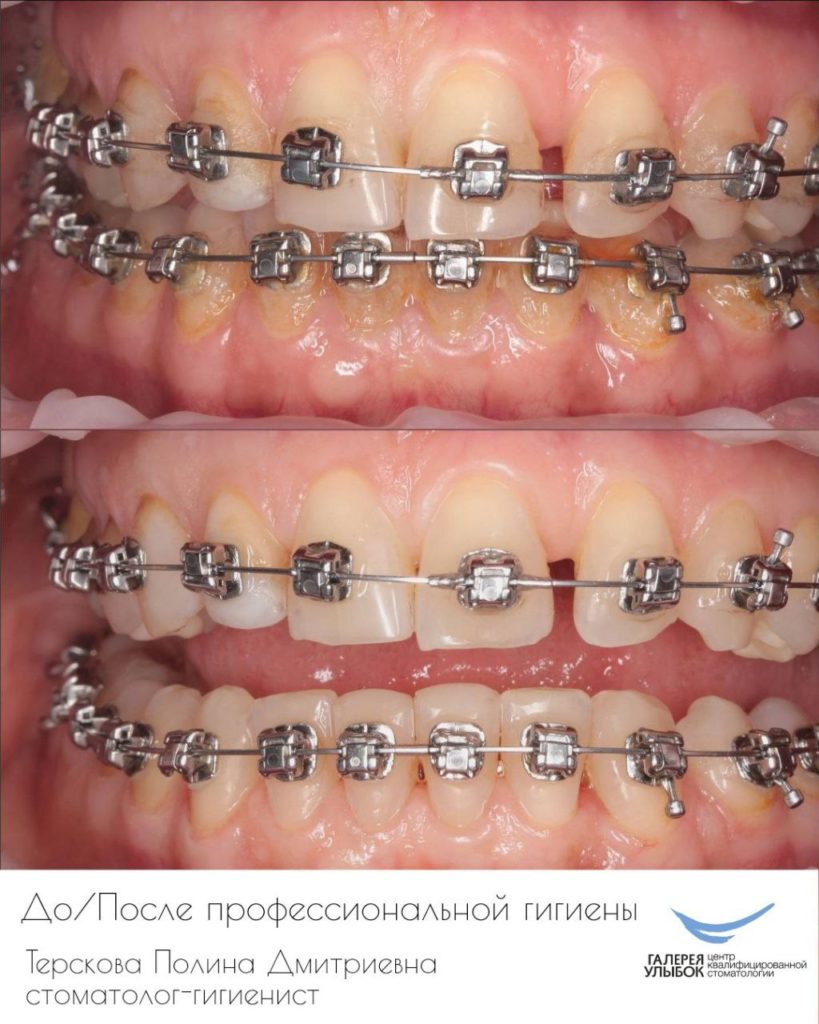

Улыбки в фотографиях: типы и комической моменты

Раздел: Фотогалерея мыслей